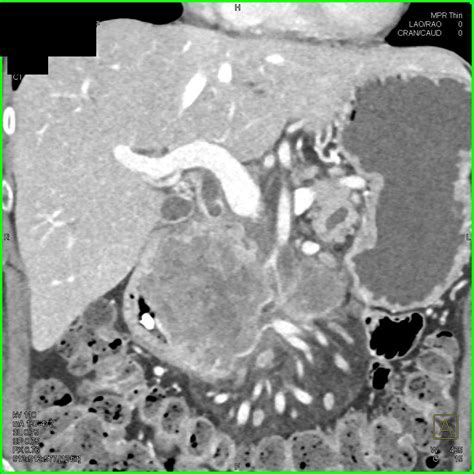

Pancreatic adenocarcinoma is a particularly aggressive form of pancreatic cancer that originates in the exocrine cells of the pancreas. Early detection and accurate diagnosis are crucial for effective treatment. One of the most important diagnostic tools for pancreatic adenocarcinoma is the Pancreatic Adenocarcinoma CT Scan. This imaging technique provides detailed images of the pancreas and surrounding tissues, helping healthcare professionals to identify tumors, assess their size and location, and plan appropriate treatment strategies.

A Pancreatic Adenocarcinoma CT Scan is a non-invasive imaging procedure that uses X-rays to create detailed cross-sectional images of the body. These scans are particularly useful for diagnosing pancreatic adenocarcinoma because they can:

• Detect tumors in the pancreas.

• Determine the size and location of the tumor.

• Assess the extent of the cancer's spread to nearby organs and lymph nodes.

After the Pancreatic Adenocarcinoma CT Scan, a radiologist will review the images to look for any signs of pancreatic adenocarcinoma. The results will be sent to the referring physician, who will discuss them with the patient. The scan results can provide valuable information, including:

• The presence and location of any tumors.

• The size and shape of the tumor.

• Whether the tumor has spread to nearby organs or lymph nodes.

• Any other abnormalities in the pancreas or surrounding tissues.